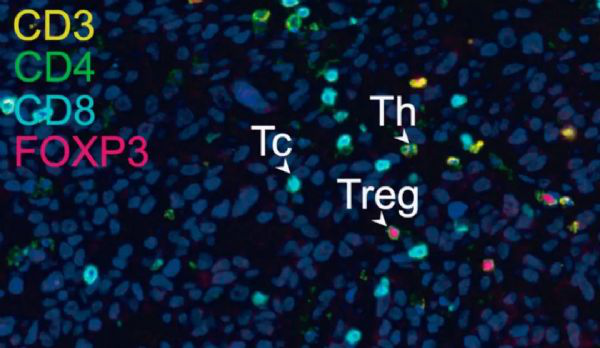

肿瘤组织里面存在多种不同的T细胞

之前的大量研究表明,肿瘤里面的浸润T细胞(TILs)是有高度的异质性的。通过实验研究,Newell团队也发现肺癌和肠癌患者的肿瘤浸润性杀伤性T细胞也存在高度的异质性。并不是所有的CD8+ 肿瘤浸润T细胞都是特异性识别肿瘤表面的抗原的,有些旁观者 CD8+ 肿瘤浸润T细胞特异性识别癌症不相关的抗原决定簇。

侵润T细胞示意图

总的来说,这个研究证实人体肿瘤组织中不仅有肿瘤特异性的CD8+ 肿瘤浸润T细胞,还有大量与肿瘤无关的旁观CD8+ 肿瘤浸润T细胞。